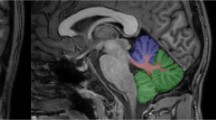

Gadolinium (Gd)-based contrast agents (GBCAs) are widely used to improve diagnostic accuracy of magnetic resonance imaging (MRI). Especially, in patients with multiple sclerosis (MS), repeated GBCA-enhanced MRI of the central nervous system is recommended at the time of diagnosis, during follow-up, while on- or off-therapy, and when intercurrent diseases and side effects such as progressive multifocal leukoencephalopathy are suspected [1,2,3]. Gd-enhancement in cerebral or spinal MS lesions indicates disruption of the blood–brain barrier which is a surrogate for recent and active inflammation. Since 2013, a number of studies demonstrated Gd retention, apart from MS lesions, in the cerebellar dentate nucleus (DN) and, to a much lesser degree, the basal ganglia as a result of repeated intravenous GBCA injections [4,5,6,7,8,9,10]. It has been shown that linear GBCAs are more likely to accumulate than macrocyclic agents [10,11,12,13,14,15,16] and that the chemically less stable linear non-ionic (e.g., gadodiamide (Gd-DA, Omniscan®)) are more likely to accumulate than the more stable linear ionic GBCAs (e.g., gadopentetate dimeglumine (Gd-DTPA, Magnevist®)) [17, 18].

Classically, Gd retention in the DN is visualized on unenhanced T1-weighted MRI and is measured as a relative signal intensity increase in the respective DN-to-comparator ratio [4,5,6,7,8,9,10,11,12], preferably the DN-to-pons signal intensity ratio (DPSIR) [19]. On the other hand, transcranial brain sonography (TCS) sensitively detected tissue alterations caused by the deposition of trace metals, neurodegeneration, and calcification of deep brain structures, including the DN [20,21,22,23,24]. So far, it is unclear whether chronic gadolinium deposition in the brain may be associated with changes of echogenicity on TCS or neurological or neuropsychological deficits. Here we studied 34 MS patients who had received 2–28 (median, 11) MRI scans with application of linear ionic and nonionic GBCAs. The main goal of the present study was to test the hypothesis that the change of DPSIR corresponds to change of DN echogenicity on TCS. In addition, we analyzed whether an increase in the DPSIR after multiple GBCA administrations may be related to signs of cerebellar dysfunction.

The review and quantitative analysis of unenhanced T1-weighted images were done by a radiologist (H.M.) with 5 years’ experience in brain MRI who could in uncertain cases consult a board-certified neuroradiologist (A.G.) with 25 years’ experience in brain MRI, both being blinded to clinical and TCS data of the patients. The T1-signal intensity increase was assessed according to the recommendations of the European Gadolinium Retention Evaluation Consortium and the European Society of Neuroradiology [19]. For measuring the signal intensity in unenhanced T1-weighted images on the PACS workstation (IMPAX 6; Agfa HealthCare), a region of interest was manually drawn around the dentate nucleus and in the pons. T2-weighted sequences were available to help localize the nuclei. The regions of interest allowed the measurement of the averaged signal intensity in an individually defined area. By dividing the averaged signal intensity of the DN by the averaged signal intensity of the pons, the DPSIR was determined (average value of bilateral DN). Ultimately, changes in DPSIR over time were calculated by subtracting the DPSIR at the first assessable MRI from that at the last MRI. Since digitized MRI data sets were present in our database since July 2005, calculation of DPSIR changes was restricted to MRI scans registered since then. Analogously, the globus pallidus internus (GPi)-to-thalamus signal intensity ratio (GTSIR) and GTSIR differences were calculated.

Once real-time TCS examination was being performed, the MRI volume was also being scrolled automatically by the system, showing the same planes. This allowed then for the clear delineation of the ROIs of DN and GPi, being evident on MRI, also in the corresponding plane on TCS (see Supplementary Material 1). The TCS images of DN and GPi were saved for digitized analysis. To quantify the echo-intensity of DN and GPi, off-line digitized image analysis was performed using a validated MATLAB-based software tool [27]. This tool pre-assesses the overall image quality before starting the analysis of distinct structures, yielding a normalized echo-intensity measure of the target structure in the referring ROI. Mean values of bilateral DN, and of bilateral GPi, echo-intensity per patient were used for further analyses.